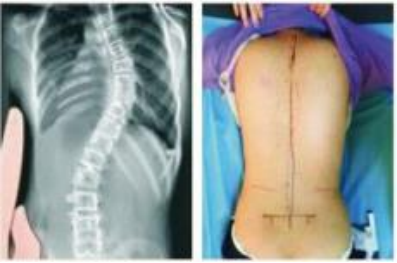

治疗前后对比图: